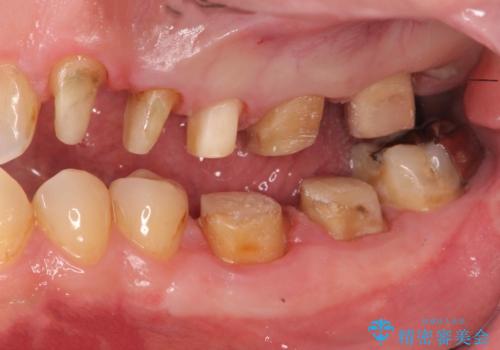

銀歯・虫歯・治療途中の歯を治していきたい

- 銀歯・虫歯・治療途中の歯を治していきたい、セラミックの歯にしたい!と希望され来院されました。

銀歯の下で再発した虫歯や、根尖病変等、多々の問題が認められましたがひとつづつ丁寧に改善し、長期的な予後の見込めるセラミック治療を行っていきます。